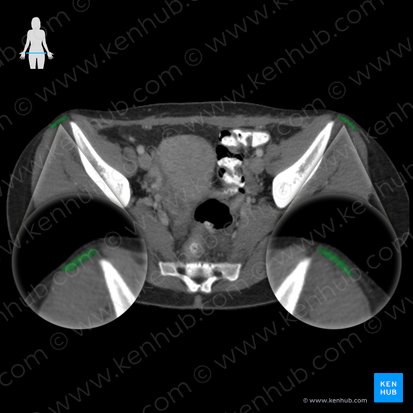

Der M. tensor fasciae latae entspringt an der Crista iliaca und Spina iliaca anterior superior des Os ilium.

Distal strahlen seine Fasern gemeinsam mit Ansatzsehnen des Gluteus maximus und der Aponeurose des Gluteus medius in die Fascia lata ein, einer Faszie an der Außenseite des Oberschenkels.